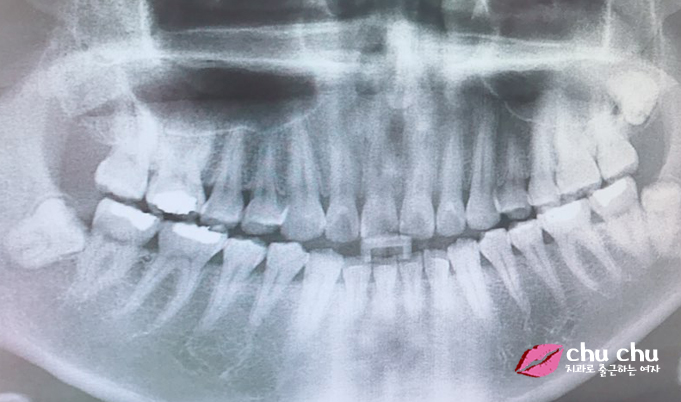

![[ 연세굿데이 교정 ] 우리 직원이 달라졌어요 - 돌출입치아교정 start 관련 이미지 2](https://pub-9f2bb3498faf4d1d8714b41df24753e3.r2.dev/content/clinics/archive/5hurea2jnb/naver_blog/eunkyo3370/assets/by_hash/4b8e475afb919265c26eff9dcc70bca7cf8a3bba28d4a09749e5f6a9828b93a4.jpg)

그럼 현재 치아 상태는 어떻고 돌출입치아교정은 어떻게 계획을 잡고 들어갈까요?

원장님께 직접 여쭤봤습니다.

전형적인 돌출입이지만 이가 고르지 않은건 심하지 않은 편입니다. 3~4개월 정도 가지런히 하는 기간을 거치고 그 이후에 돌출입을 집어 넣게 됩니다.

돌출입치아교정은 적당히 들어가게 해야 되는데 ..